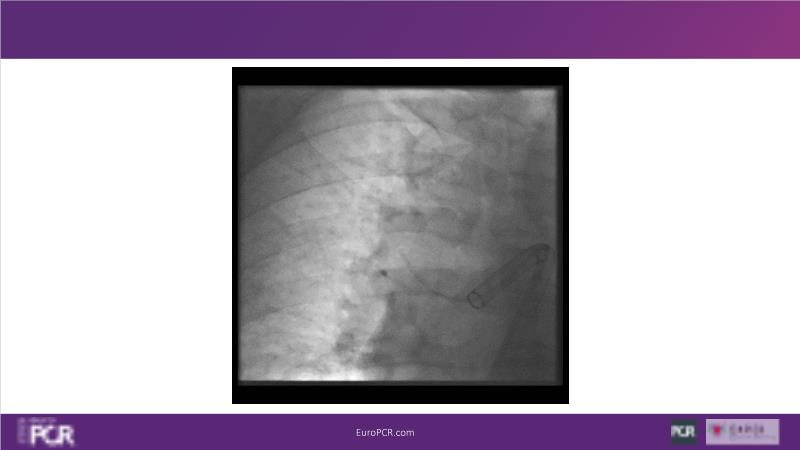

Why mechanical thrombectomy should be considered in the management of acute pulmonary embolism

In this EuroPCR 2024 session, study the case of a patient with high-risk pulmonary embolism and another with intermediate to high-risk pulmonary embolism, delve into discussions on clinical evidence for mechanical thrombectomy in pulmonary embolism, acquire skills to evaluate eligibility for mechanical thrombectomy, and learn how to integrate such technique in local pulmonary embolism patient pathway.